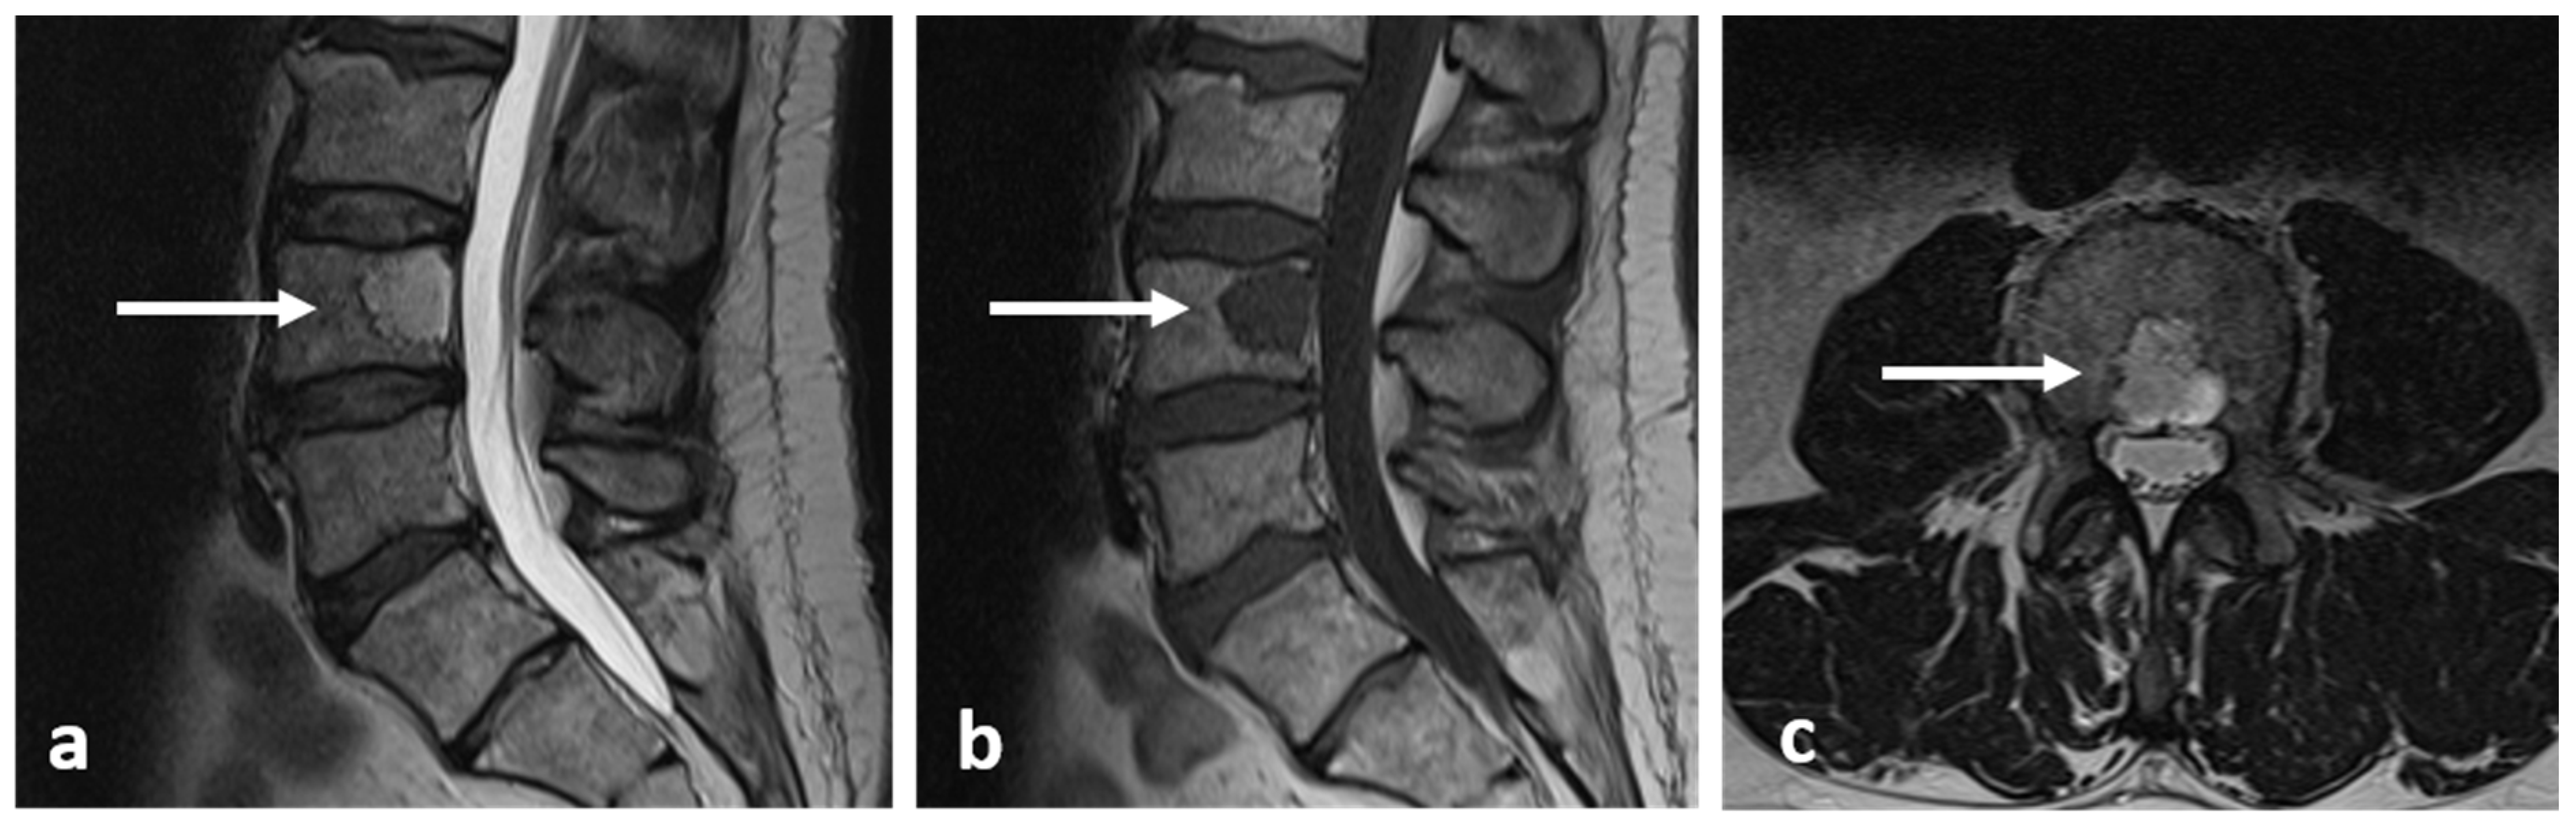

3.9. Aneurysmal Bone Cyst

| Aneurysmal bone cyst | Expansile lytic lesion with internal bone septations. | Fluid—fluid levels within the cysts, high T1 signal within layering fluid content due to haemorrhage. |